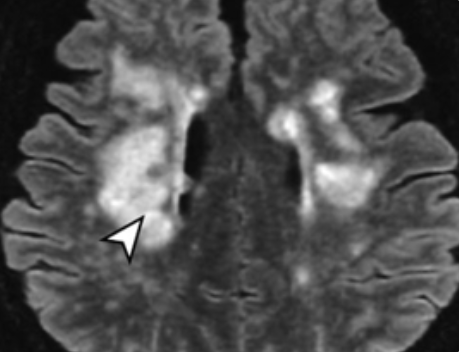

섬망은 단순한 치매나 우울증과는 차원이 다른, 급성 의식 변화와 인지 기능 장애를 특징으로 하는 심각한 신경정신 질환입니다. 기저 질환, 약물 부작용, 심각한 영양 결핍 등 다양한 원인에 의해 뇌 기능이 갑자기 비정상적으로 작동하는 '뇌 기능의 비상사태'로 간주됩니다.

섬망은 뇌 세포 간의 정상적인 통신이 방해받거나, 뇌의 에너지 대사에 문제가 생길 때 발생할 위험이 높아집니다. 따라서 뇌 세포 구성과 신경 전달 물질 합성에 필수적인 영양소를 보충하는 것이 중요합니다.

섬망은 감염, 탈수, 약물 과다, 뇌졸중 등 명확한 원인이 있는 경우가 대부분입니다. 영양제 복용에 앞서 즉시 병원을 방문하여 원인을 치료하는 것이 환자의 생명과 예후에 결정적입니다.